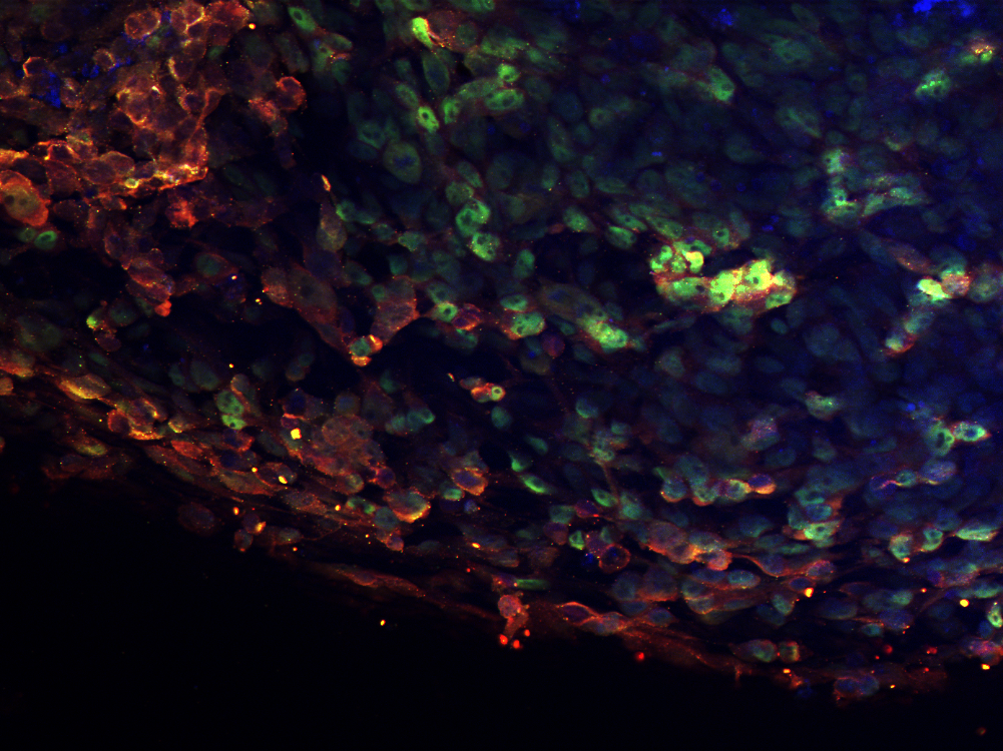

We’ve challenged all Doctoral Training Alliance (DTA) PhD students to submit an image with a short blurb that represents their current research project or topic area for our annual ‘Images of Research’ competition.

All entries will be displayed at this year’s Summit and again at the Summer Schools, where prizes will be awarded for a people’s choice, judge’s winner and runner up.